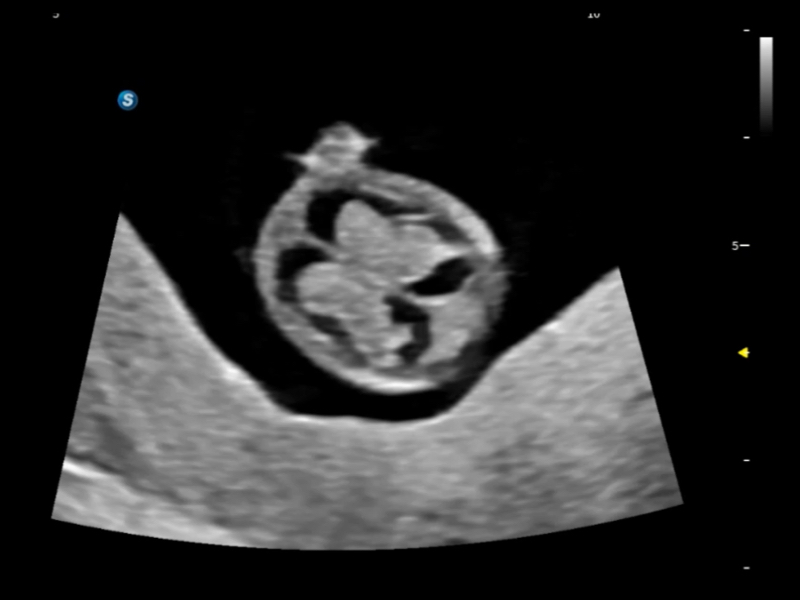

丰富的血流动力学检测技术,可在不同医疗场景中高效捕捉血流信号,助力临床诊疗。

在传统血流的基础上优化扫查和算法策略,能够更好的抑制组织信息,提炼红细胞运动信息,得到更高帧频,高灵敏度和分辨率的血流信号,还原更真实的血流动力学。

通过创新的Matrix E自适应滤波算法,能有效滤除软组织和噪声信号,最大限度保留超低速微细血流的信号;结合超长时间域算法,极大提升细微血流的敏感性和空间分辨率,更真实的反应组织、包块的血流灌注情况。